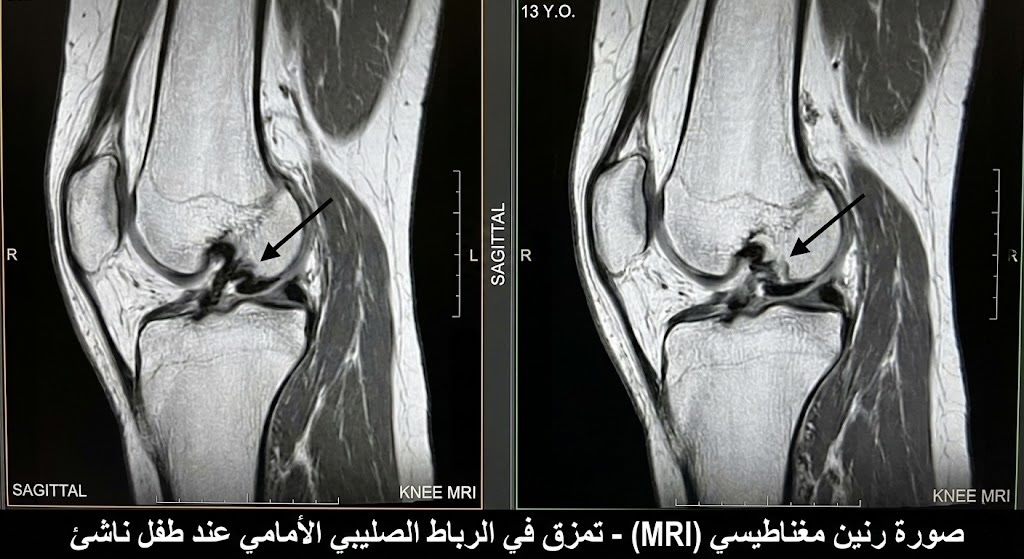

الرنين المغناطيسي (MRI)

الرنين المغناطيسي هو الفحص الذهبي لإصابات الأنسجة الرخوة – يعني الأربطة والغضاريف والعضلات. لو الأشعة العادية طلعت سليمة بس الطفل لسه عنده ألم وتورم، بنعمل رنين عشان نشوف حالة الأربطة والغضروف الهلالي بتفصيل كامل. الرنين المغناطيسي كمان بيبين لنا إصابات الإجهاد (Stress Injuries) اللي مش بتظهر في الأشعة العادية.

إصابات الرباط الصليبي الأمامي (ACL Injuries)

زمان كنا بنفتكر إن إصابات الرباط الصليبي مش بتحصل عند الأطفال – بس الدراسات الحديثة أثبتت إنها بتزيد بشكل كبير، خصوصاً عند الأطفال من سن 10 سنين فما فوق. الفرق إن عند الطفل، الجراحة لازم تتم بطريقة خاصة تحافظ على لوحة النمو (Physeal-Sparing Technique) عشان ما نأثرش على نمو العظم.